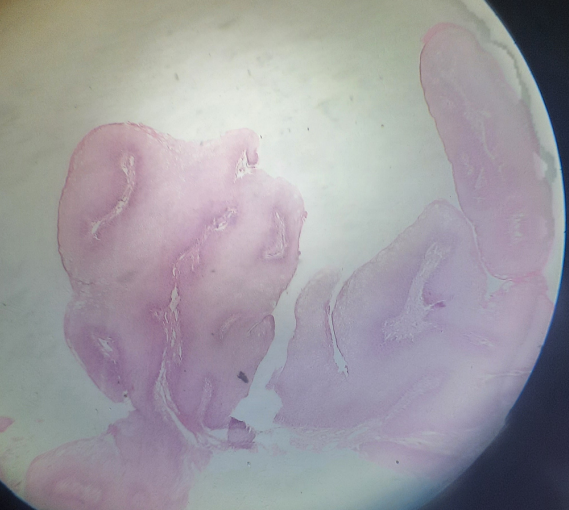

4

Transitional cell carcinoma of bladder

Papillary malignant tumor that shows vascularized CT by several layers of transitional cells showing pleomorphism